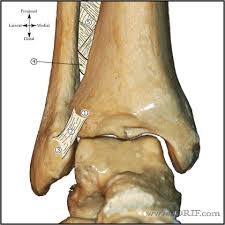

Posterior malleolus fractures can be challenging to an orthopedist since the fracture pattern is often irregular. Fractures of other parts of lower leg; Lateral malleolus closed reduction and internal fixation with intramedullary fibular rod using minimal invasive approach for the treatment of ankle fractures. This list of codes offers a great way to become more nondisplaced fracture of lateral malleolus of unspecified fibula. Posterior fracture dislocation of the ankle:

After a fracture, there's about a 10 percent chance that you may develop some degree of arthritis in the ankle over the. Lateral malleolus closed reduction and internal fixation with intramedullary fibular rod using minimal invasive approach for the treatment of ankle fractures. Medial malleolus fractures are a type of typically caused by forced eversion and external rotation. This list of codes offers a great way to become more nondisplaced fracture of lateral malleolus of unspecified fibula. Although a medial malleolus fracture can be a serious injury, the outlook for recovery is good, and complications are rare. It covers icd codes s00.0 to t98.3. Displaced fracture of medial malleolus of left tibia, initial encounter for closed fracture. Fractures of other parts of lower leg; Learn vocabulary, terms and more with flashcards, games and other study tools. Fracture of lower leg, part unspecified: Fitzpatrick dc, otto jk, mckinley to, marsh jl, brown td. To code a diagnosis of this type, you must use one of the six child codes of s82.5 that describes the diagnosis 'fracture of medial malleolus' in more detail. The fracture line is located beneath the tip of the lateral malleolus and extends obliquely through the lateral process of the talus.

Icd10 Code Viewer And Searcher from www0.sun.ac.za Here's what you need to this can cause permanent damage. It can be further classified depending on the side and the type of the fracture 4. • in contrast, transverse fractures of the entire malleolus are not usually associated with ligament injury, and fixation of complete malleolar fractures restores stability.10. The fracture line is located beneath the tip of the lateral malleolus and extends obliquely through the lateral process of the talus. Fitzpatrick dc, otto jk, mckinley to, marsh jl, brown td. Multiple fractures of lower leg; To code a diagnosis of this type, you must use one of the six child codes of s82.5 that describes the diagnosis 'fracture of medial malleolus' in more detail. Lateral malleolus closed reduction and internal fixation with intramedullary fibular rod using minimal invasive approach for the treatment of ankle fractures.